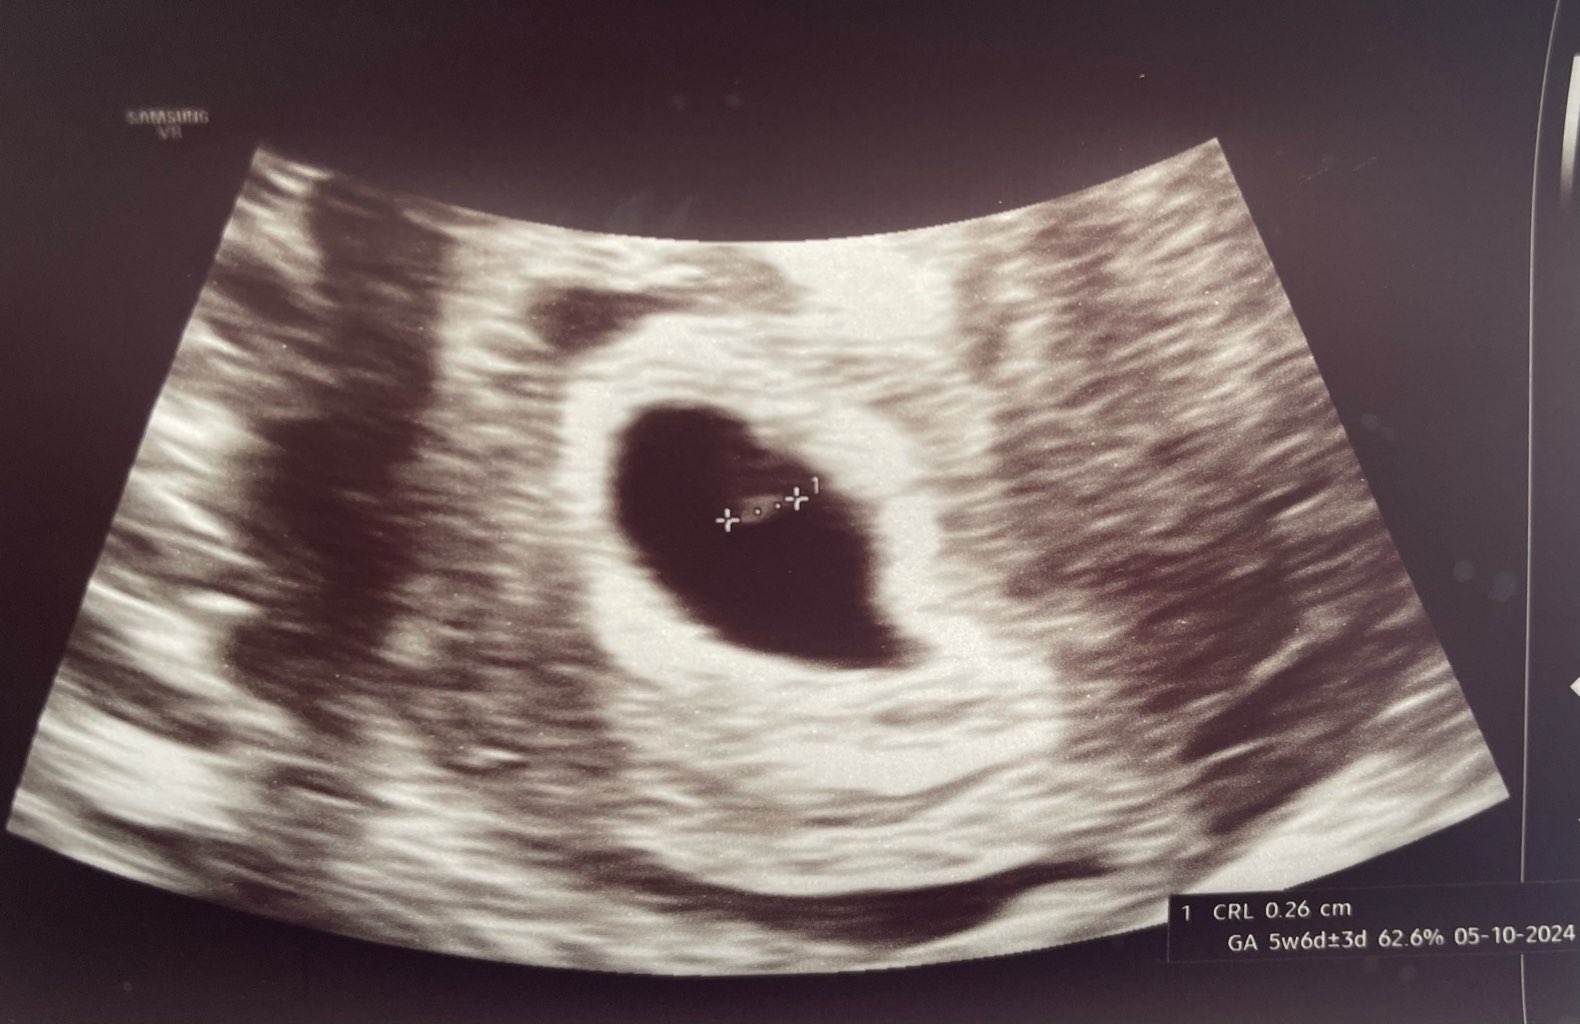

PIĘKNE WIEŚCIZarodek 2,6mmjeszcze bez serduszka.

Z USG wychodzi 5+5 wg pani ginekolog, według OM 5+2, ale wpisała mi termin porodu z okresu

W środę idę na NFZ, mam nadzieję, że zobaczę serduszko na walentynki![]()